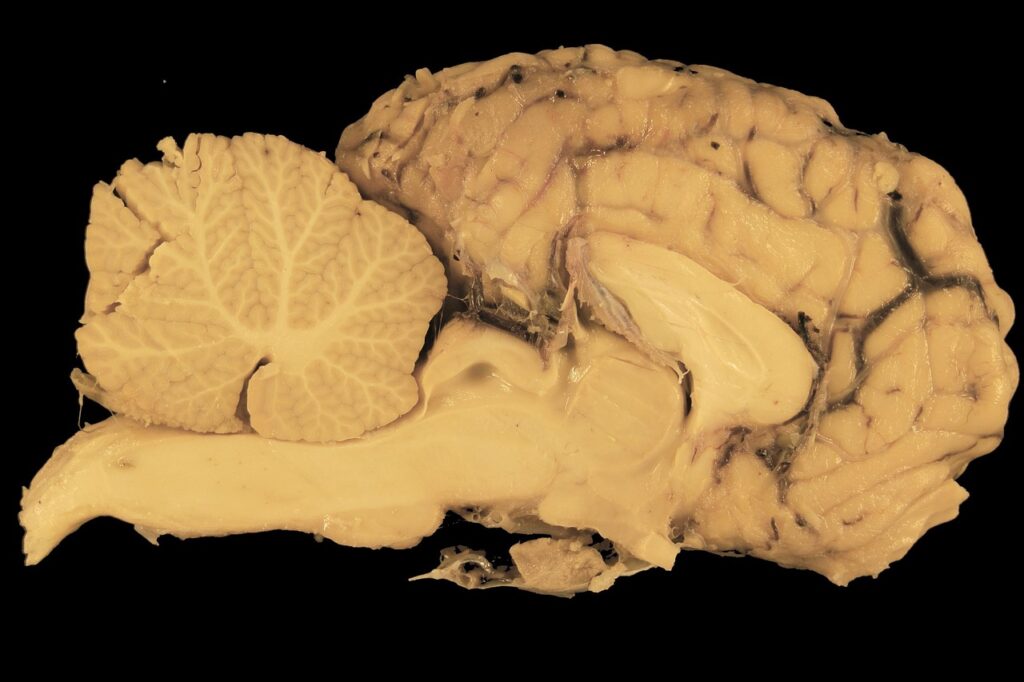

5) Mammals

- Neocortex: Complex cognition, problem-solving.

- Corpus Callosum: Connects brain hemispheres.

B. Encephalization (~320 MYA–Present)

- Brain-to-Body Size Ratio: Increased in mammals and birds.

- Cortical Folding: Maximizes surface area (e.g., human gyri and sulci).